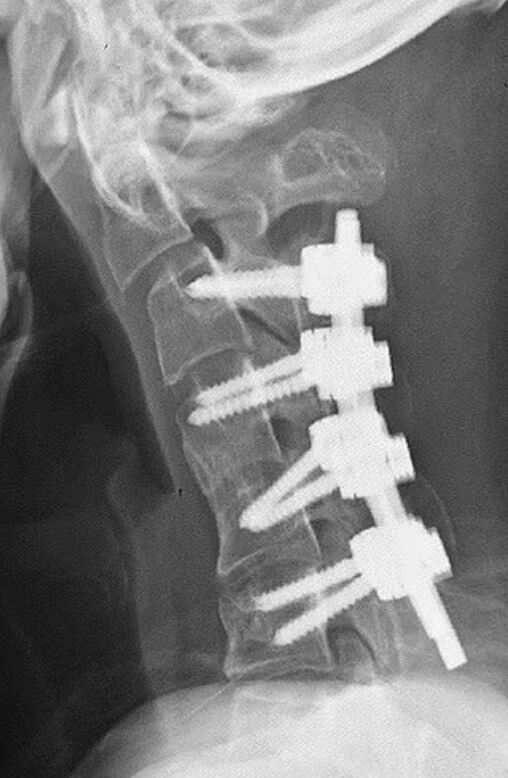

Omurgasının düzelebilmesi için birçok operasyon geçiren adamın omurgasından küçük parçalar alınarak boynunda oluşan yara benzeri doku temizlendi. Daha sonra duruşun düzeltilmesi için boyun kemiklerine vida ve metal çubuklar yerleştirildi.

Operasyondan önce yutma problemi yaşayan gencin, ameliyattan 6 ay sonra iyileşerek boynunu yatay pozisyona getirebildiği kaydedildi. Uzmanlar, hastanın rahatsızlığının boynun uzun süre yanlış pozisyonda tutulmasından ve gelişimsel bir bozukluktan kaynaklandığını bildirdi. Ayrıca, gençler arasında artan akıllı telefon kullanımının tehlikeleri konusunda farkındalığın artırılması çağrısında bulunuldu.